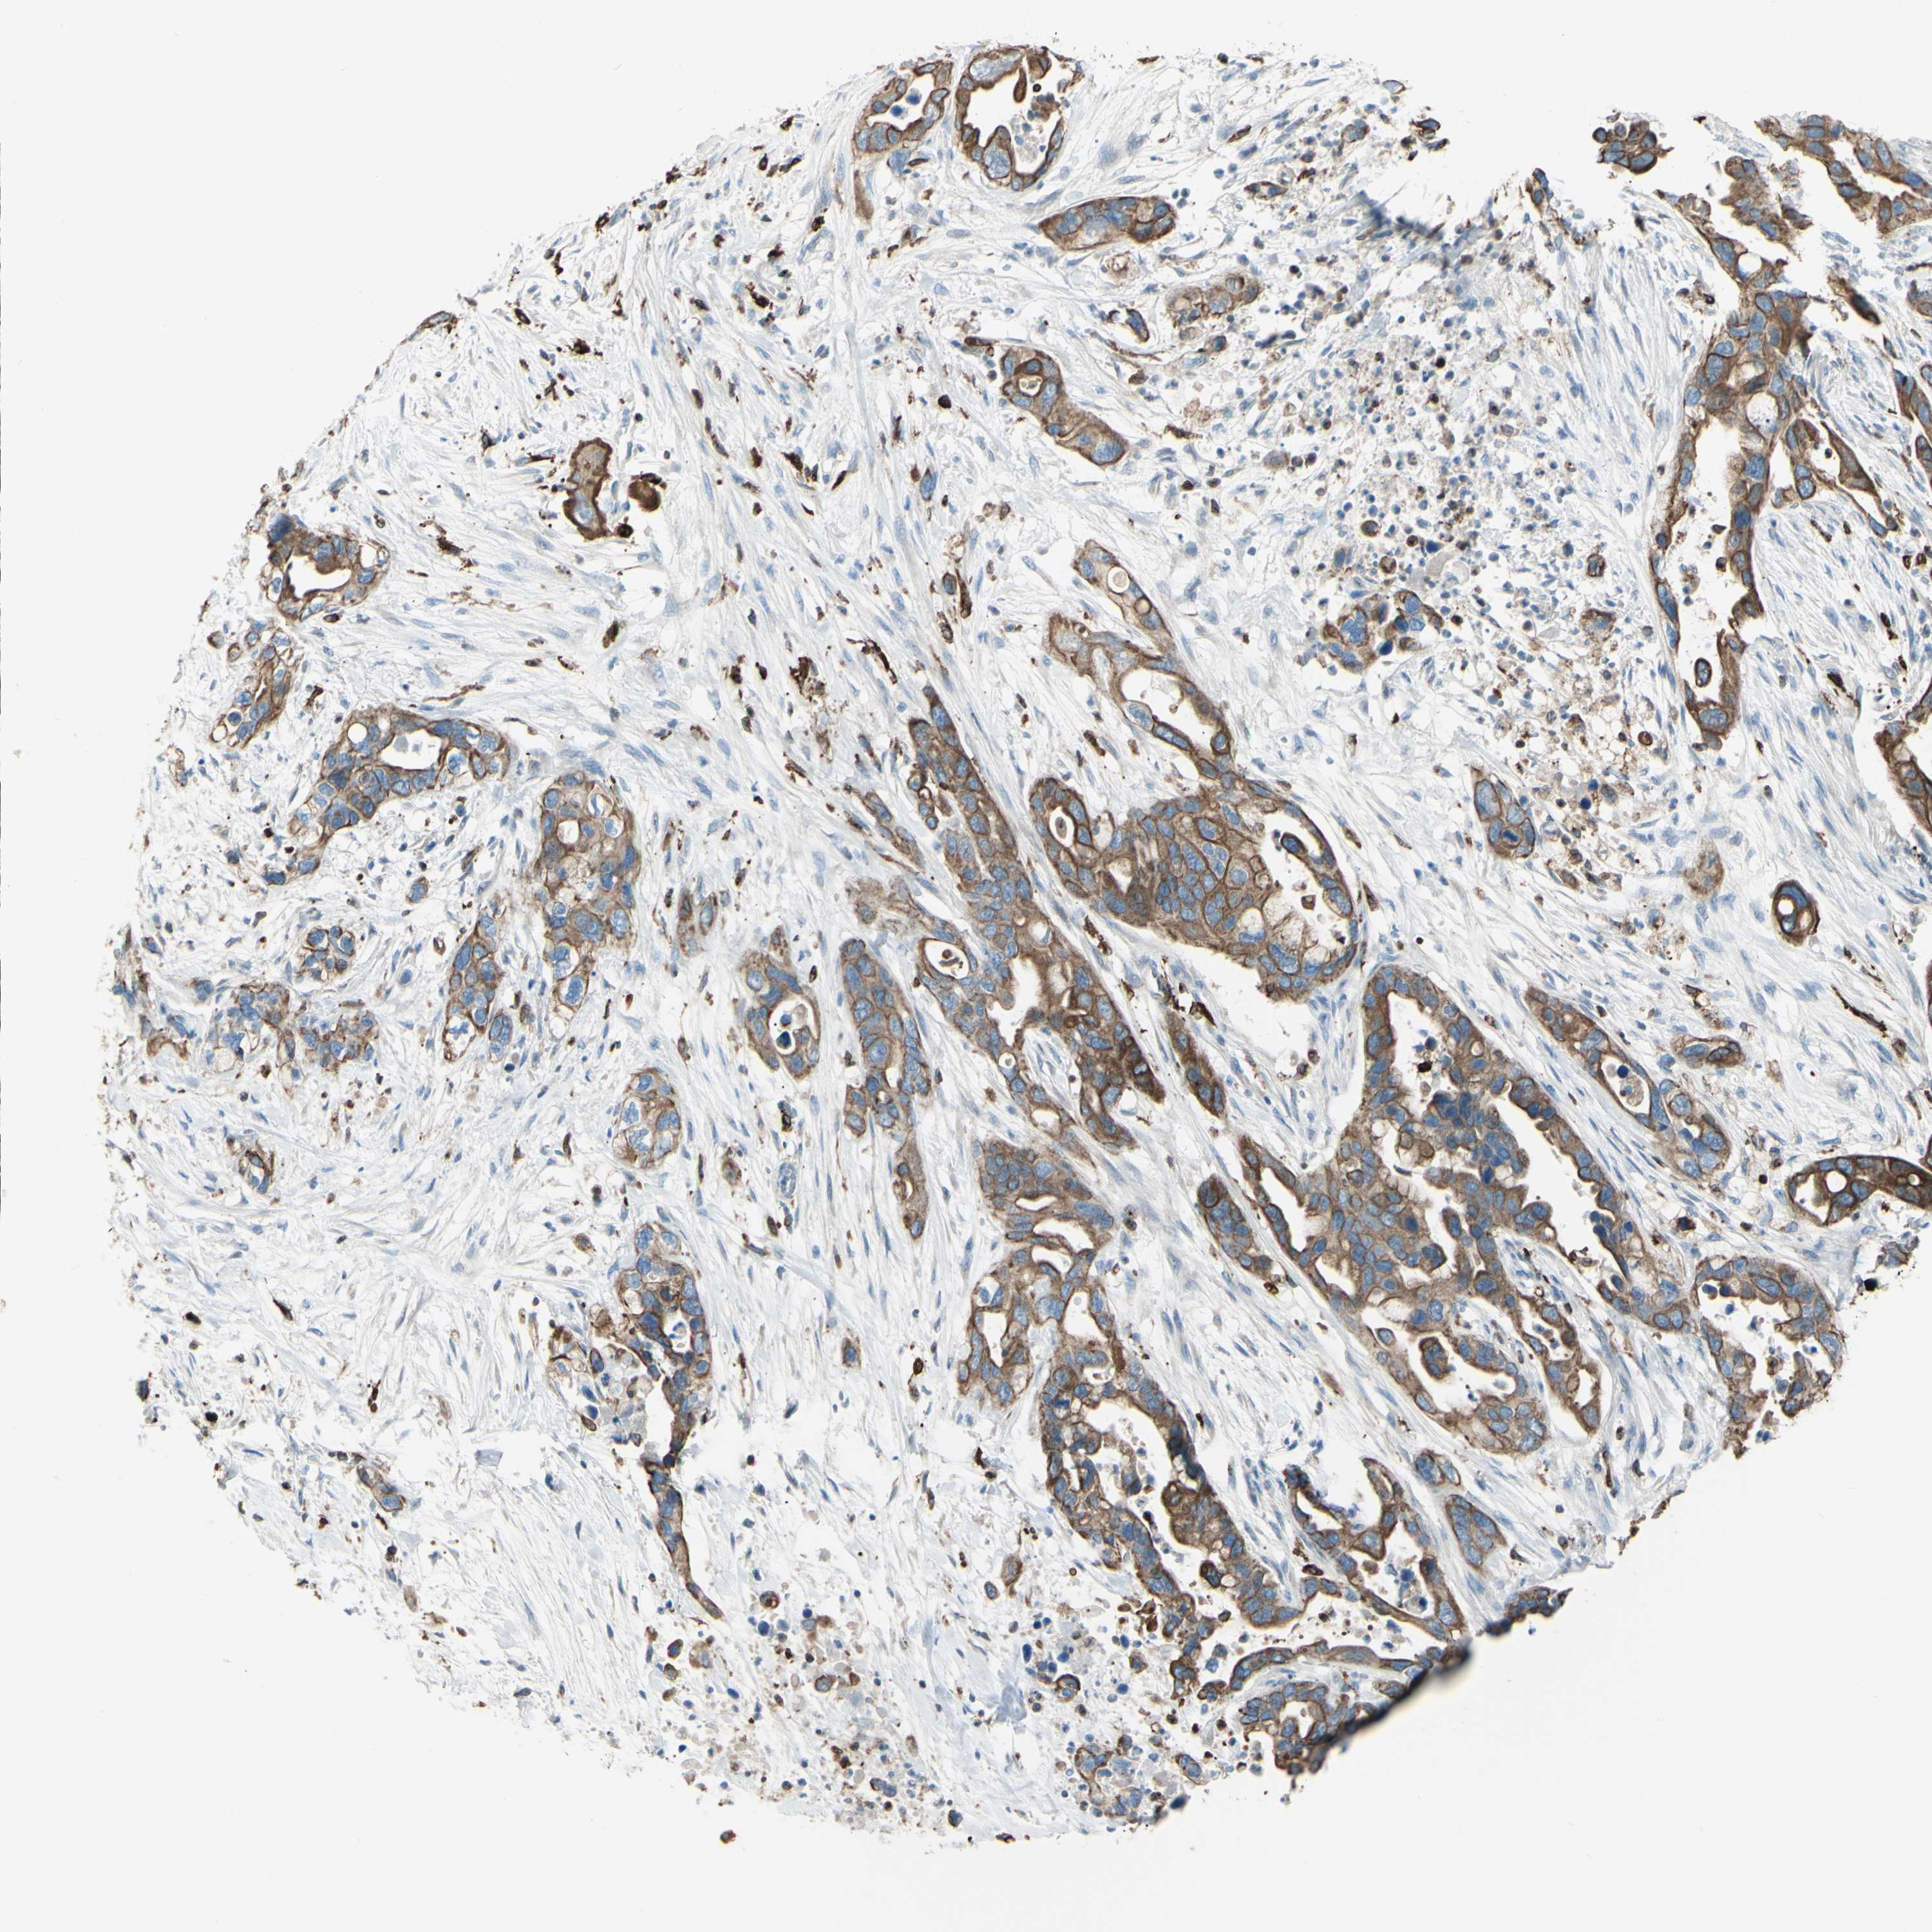

PANCREATIC CANCER - Protein expressioni

A mouse-over function shows sample information and annotation data. Click on an image to view it in a full screen mode. Samples can be filtered based on level of antibody staining by selecting one or several of the following categories: high, medium, low and not detected. The assay and annotation is described here.

Note that samples used for immunohistochemistry by the Human Protein Atlas do not correspond to samples in the TCGA dataset.

Antibody stainingi

Antibody staining in the annotated cell types in the current human tissue is reported as not detected, low, medium, or high, based on conventional immunohistochemistry profiling in selected tissues. This score is based on the combination of the staining intensity and fraction of stained cells.

Each image is clickable and will lead to virtual microscopy that enables deeper exploration of all samples and also displays staining intensity scores, fraction scores and subcellular localization as well as patient and tissue information for each sample.

Antibody HPA010592

Antibody CAB002506

Antibody CAB079994

Staining

High

Medium

Low

Not detected

Intensity

Strong

Moderate

Weak

Negative

Quantity

>75%

75%-25%

<25%

None

Location

Nuclear

Cytoplasmic/membranous

Cytoplasmic/membranous,nuclear

Adenocarcinoma, NOS

Adenocarcinoma, metastatic, NOS